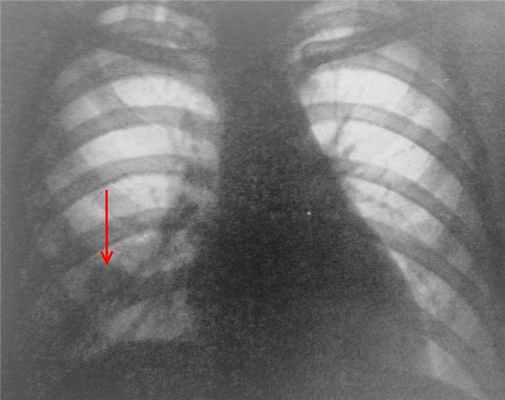

(а) При рентгенографии органов грудной клетки в ПП проекции определяется объемное уменьшение левого легкого и ателектаз нижней его доли. Следует отметить наличие бронхоэктазов в ателектазированной доле, что свидетельствует о хроническом ее коллабировании.

(б) У этого же пациента при КТ с контрастным усилением в нижней доле левого легкого визуализируется эндобронхиальный узелок пониженной плотности с макроскопическими жировыми включениями. При хирургическом вмешательстве была выявлена эндобронхиальная гамартома. В дифференциальный ряд также может быть включена и эндобронхиальная липома, однако при КТ она характеризуется наличием только участков жировой плотности. (а) При прицельной рентгенографии органов грудной клетки в ПП проекции в верхней доле левого легкого определяются гетерогенные затемнения, а также признаки объемного уменьшения данной доли и наличия бронхоэктазов.

(б) У этого же пациента при КТ с контрастным усилением визуализируется обструкция проксимальных отделов левого верхнедолевого бронха узелком. Следует отметить наличие макроскопических жировых включений в структуре данного образования, что типично для гамартомы и липомы. У пациентов с эндобронхиальной гамартомой при рентгенографии органов грудной клетки чаще всего выявляют ателектаз, участки консолидации легочной ткани и бронхоэктазы.